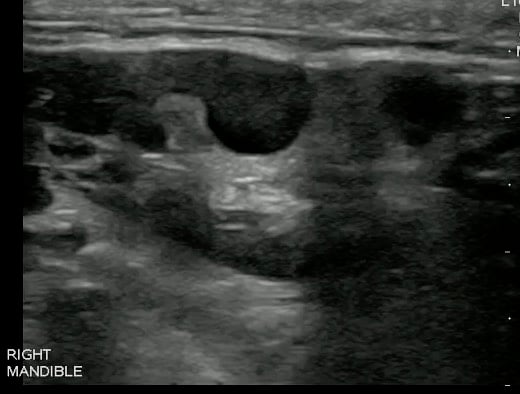

- Videos 7 and 8. Lymph nodes

- Normal lymph node

- Oval in appearance

- Echogenic hilum

- Homogenous in echotexture

- Doppler blood flow is seen branching radially from the hilum and no flow is seen in the periphery

Video 9. Color doppler on lymph node

- Figures 11 and 12. Lymph Node